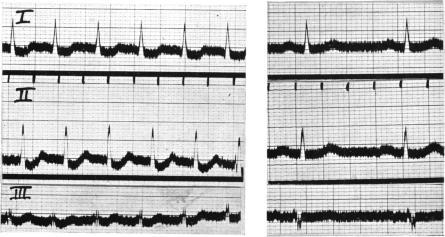

Campbell M, Elliott G A

Cardiographic Department, Guy's Hospital, and the National Hospital for Diseases of the Heart.

Br Heart J. 1939 Apr;1(2):123-60. doi: 10.1136/hrt.1.2.123.